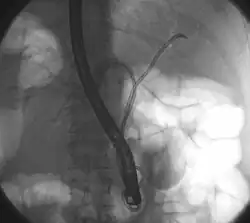

ERCP: stents placed in the left and right bile duct. At the right, the contrast that has been given before is already well-drained, making the bile ducts clearly recognizable.